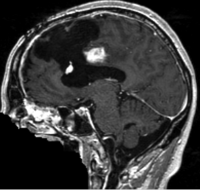

Intra-subject Brain MRI: T1 Tumor Growth / Resection Assessment

this is the fixed reference image. All images are aligned into this space lleft this is the moving image. The transform is calculated by matching this to the reference image

fixed image/target moving image

MRI, brain, head, intra-subject, T1, tumor, change assessment

• reference/fixed : T1 SPGR , 1x1x1 mm voxel size, 256x256x176 ,sagittal

• moving: T1 SPGR , 1x1x1 mm voxel size, 256x256x176 ,sagittal